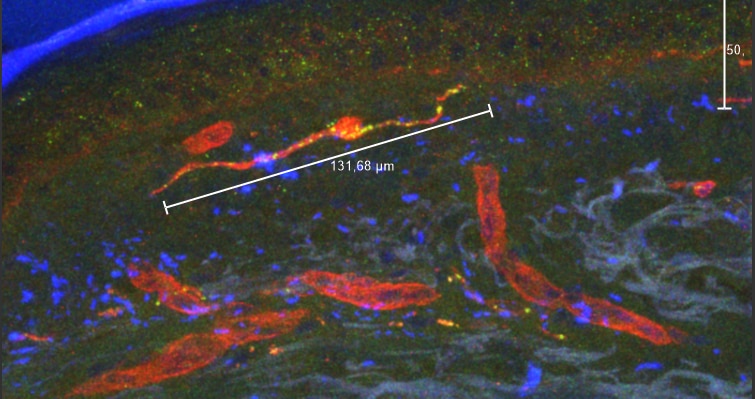

This antibody has a few additional bands in some samples, likely due to interactions between antibodies or ubiquitination of other proteins in sample

1st PGP9.5 in 1:500, 2nd antibody Cy3

Red staining = laminin + Cy5

+Dapi mounting medium

Collagen autofluorescence was a problem in some of the sections.

Zamboni Fixed, 20% sucr.